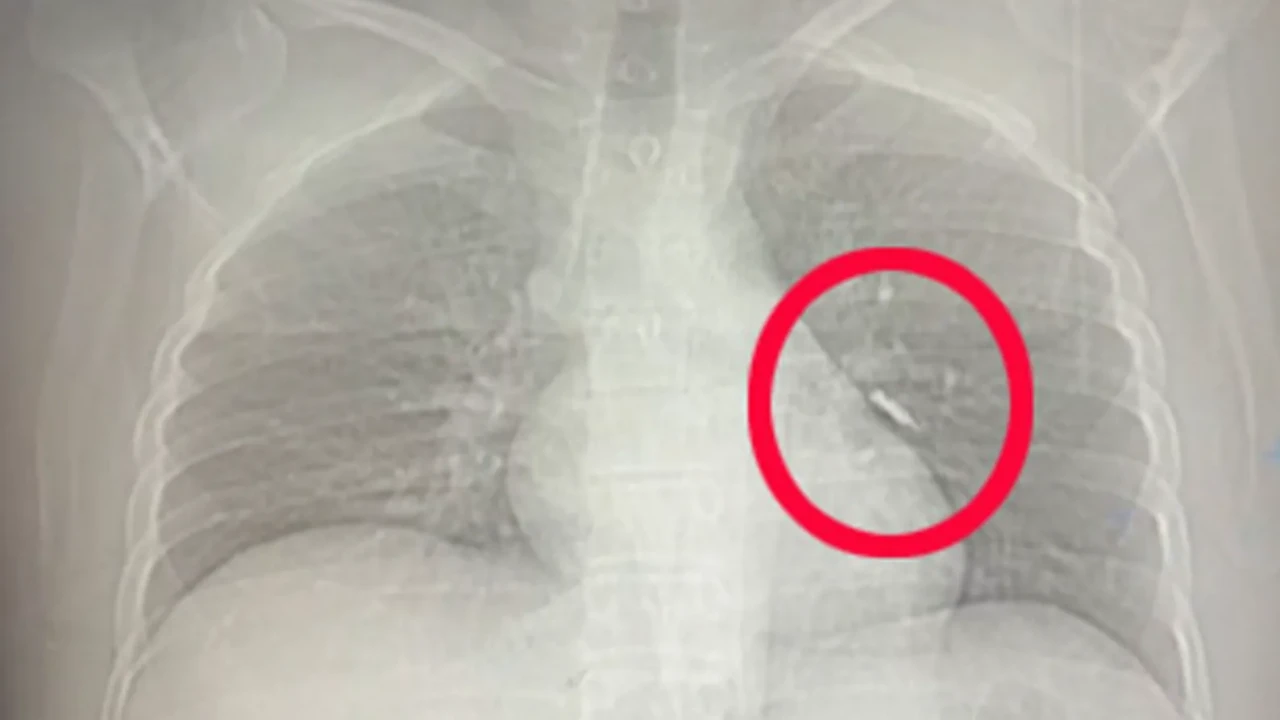

İmplant vidası, yapılan ilk kontrollerde hastanın sol akciğerinde, bronşların derin bir bölümüne saplanmış halde bulundu. Solunumu tamamen engellemeyen bu durum, yine de müdahale gerektirecek düzeyde tehlikeliydi.

Van Eğitim ve Araştırma Hastanesi’ne sevk edilen hasta, göğüs cerrahisi ekibinin gerçekleştirdiği uzun süren bronkoskopi müdahalesine alındı. Ancak vida yerinden oynatılsa da çıkarılamadı. Operasyonun ardından beklenmedik bir gelişme yaşandı: Hasta, geçirdiği şiddetli öksürükle birlikte implant vidasını midesine gönderdi. İlerleyen saatlerde, vida doğal yollarla vücuttan atıldı.